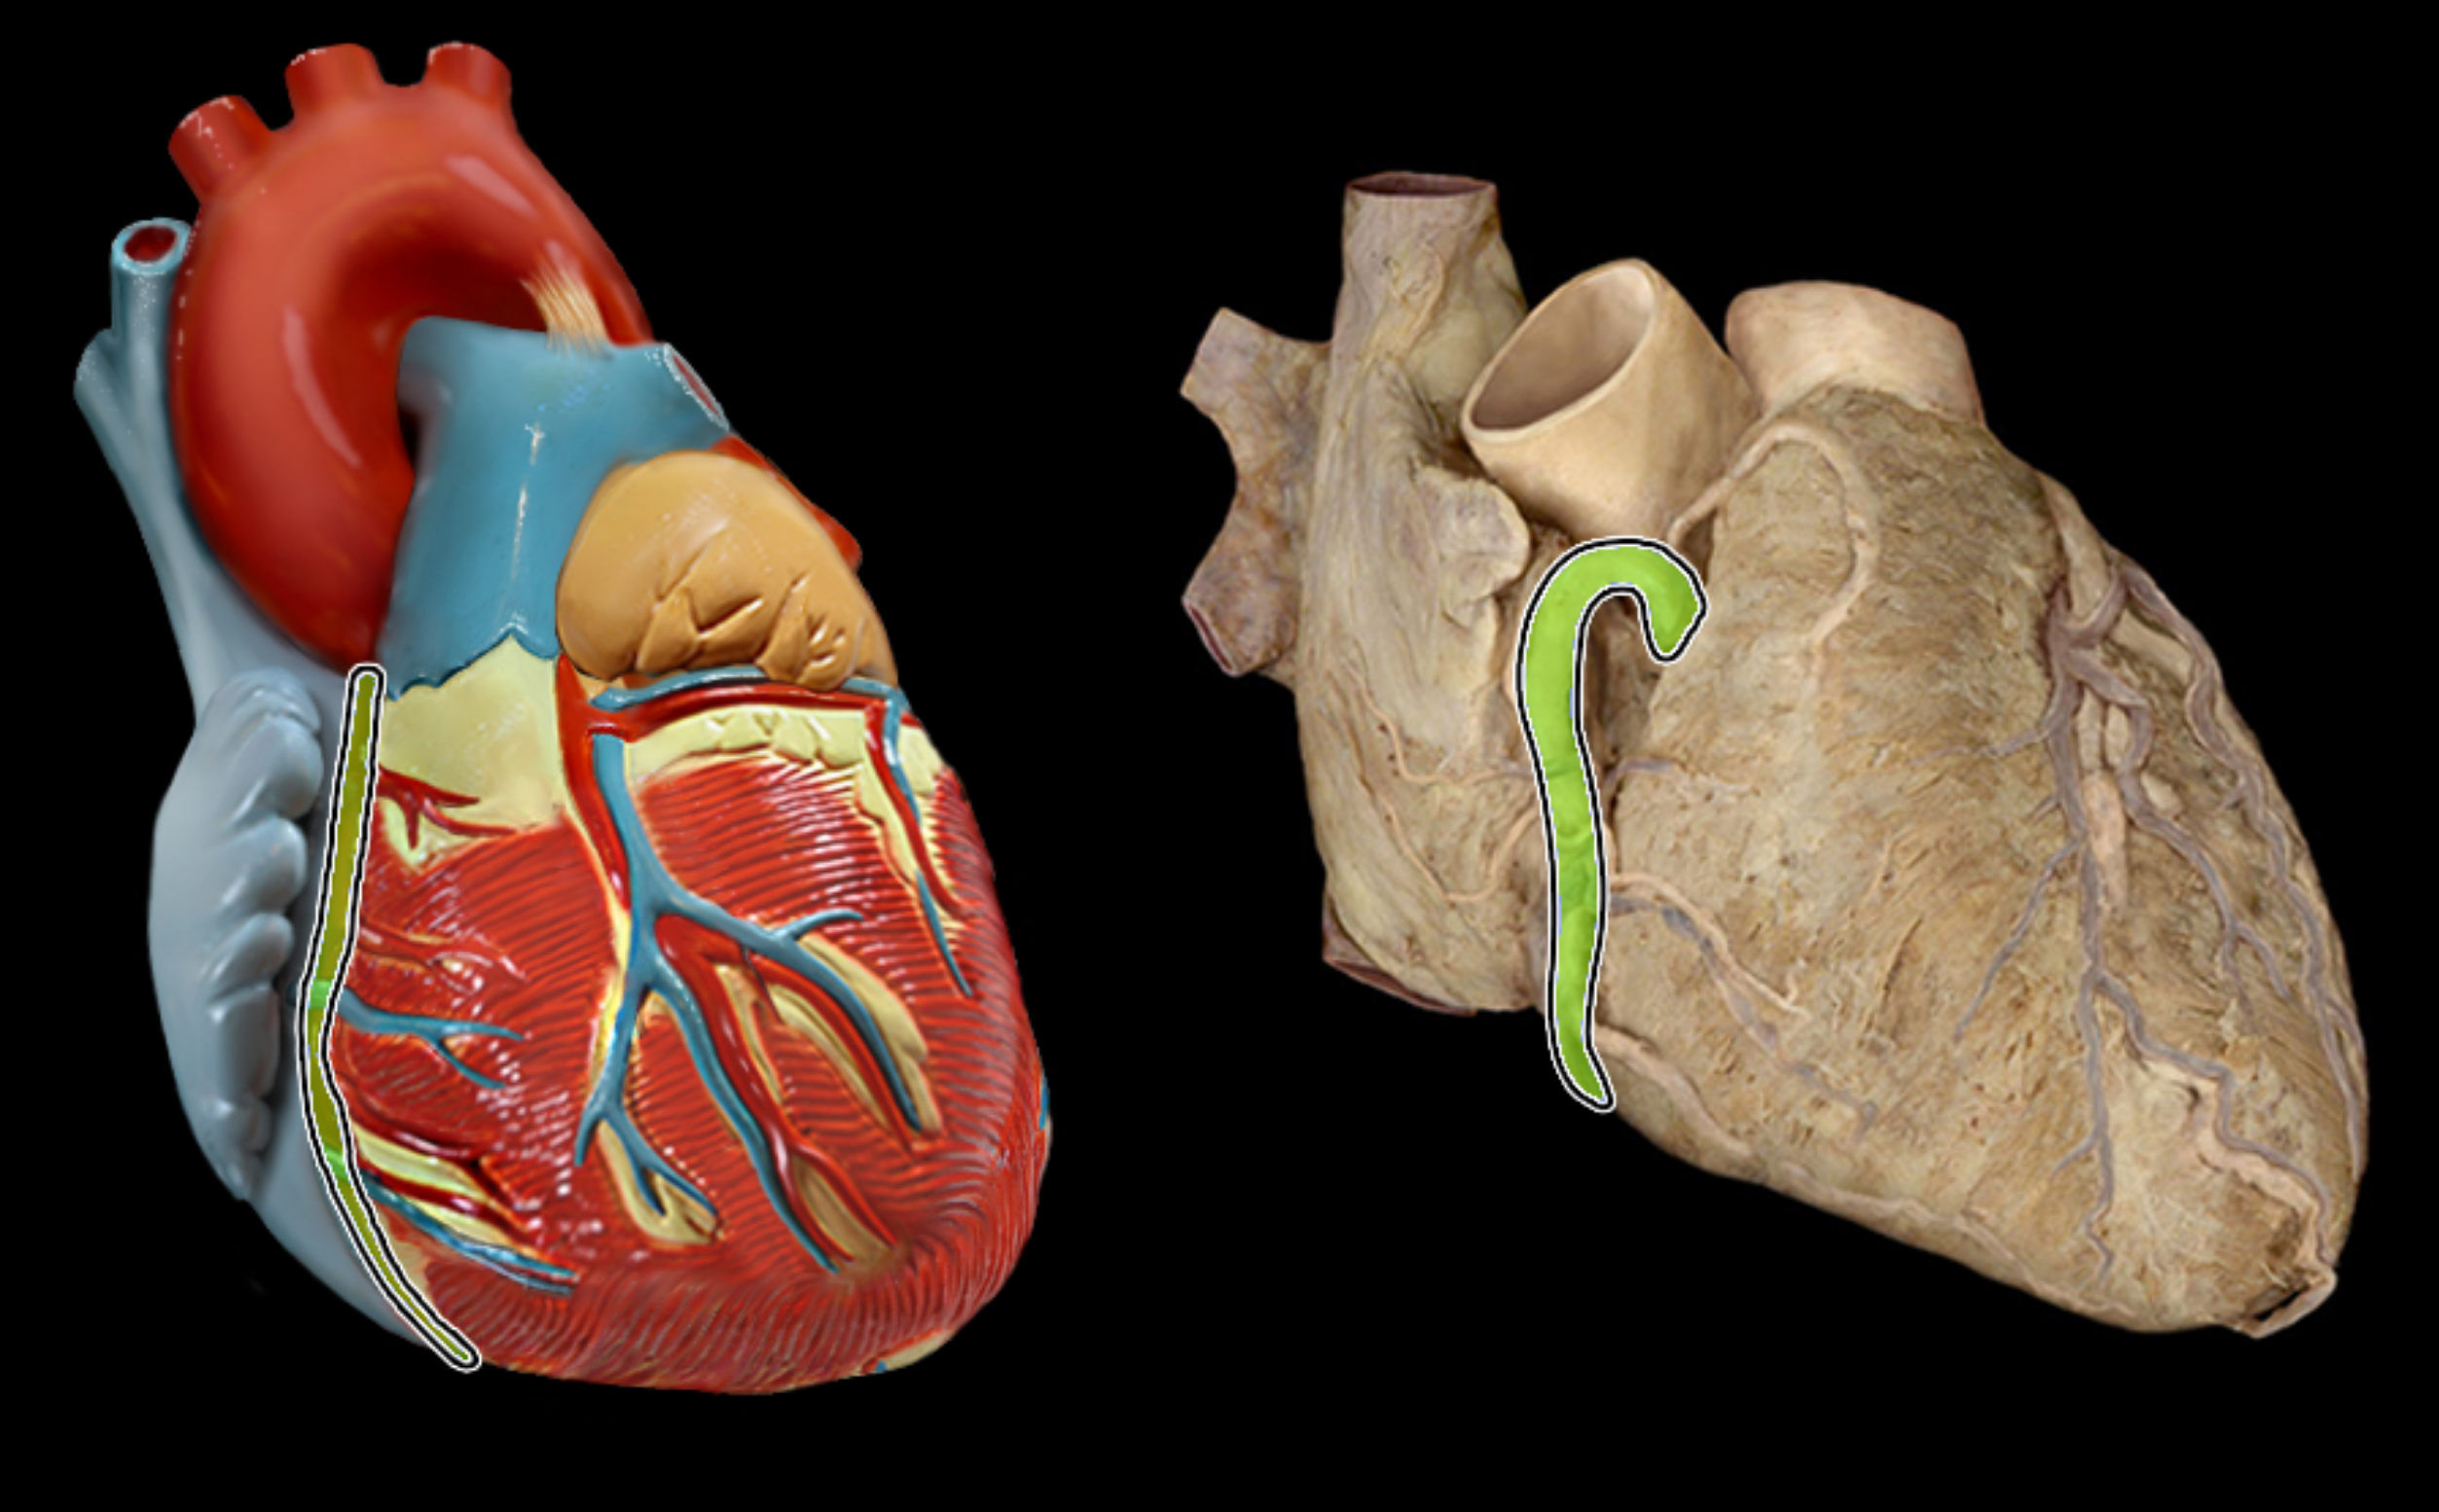

Great cardiac vein